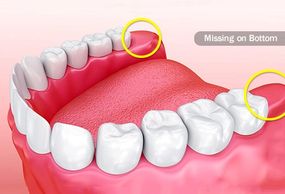

Wisdom teeth are molars, your toughest, widest teeth that grind food. But some people don’t have all their wisdom teeth. They’re the ones most commonly missing from adult mouths. Some would theorize that our jaws have changed over the years due to changes in our diet.